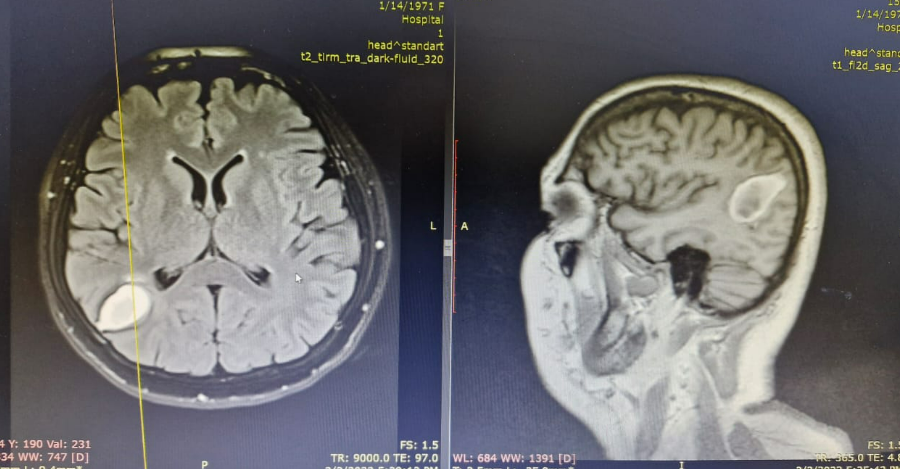

მდედრობითი სქესის პაციენტი, სამწლიანი ანამნეზით. იმყოფებოდა ჩვენს „მეზობელ“ სახელმწიფოში, სადაც ონკოლოგიური დაავადების გამო ჩაუტარდა სარძევე ჯირკვლის სექტორული რეზექცია. ონკოლოგიური სიფხიზლის გათვალისწინებით, პაციენტს უტარდებოდა დიაგნოსტიკური კვლევები, თავის ტვინის მრ კვლევით მარჯვენა თხემის წილში ნანახი იქნა მოცულობითი წარმონქამნი.

ვციტირებ პაციენტის სიტყვებს – “3 წლის მანძილზე 8-ჯერ ჩამიტარდა თავის ტვინის მაგნიტურ-რეზონანსული კვლევა, ბოლოს მითხრეს რომ სიმსივნის მე-4 სტადია მქონდა, შემომთავაზეს ოპერაციული ჩარევა, მაგრამ არ მინდოდა უცხო ქვეყანაში სიკვდილი და გადავწყვიტე სამშობლოში დაბრუნება“. საქართველოში ყოფნის პერიოდში პაციენტს განუვითარდა გენერალიზებული გულყრა, კონსულტირებულ იქნა ჩემს მიერ საქართველოს ერთ-ერთ რეგიონში. ქალბატონს შევთავაზე წარმონაქმნის ამოკვეთა, დავიწყეთ განმეორებითი კვლევები.

ჩატარებული-თავის ტვინის მრ კვლევის მიხედვით წარმონაქმნის ლოკალიზაცია შეიცვალა, თხემის ნაცვლად ვერიფიცირდებოდა საფეთქელში. დაიგეგმა ოპერაციული ჩარევა. სავარაუდო/წინასწარი დიაგნოზი იყო თავის ტვინის მეორადი სიმსივნე (ახალი მეტასტაზი), თუმცა ოპერაციული ჩარევის დროს, თავის ტვინში ნანახი იქნა 15სმ-მდე ცოცხალი სოლიტერი, რომელიც გადაადგილდებოდა თავის ტვინში.

(ტექსტი კოლეგებისთვის) სიმსივნის ინტრაცერებრული ლოკალიზაციის გამო (3 სმ კონვექსიდან), ცერებროტომიის წინ გამოვიყენეთ ულტრაბგერითი აპარატი, მიღებული სურათზე წარმონაქმნი მკვეთრად დიფერენცირდებოდა ტვინის ქსოვილისგან, რაც არ არის დამახასიათებელი თავის ტვინის პირველადი ან მეტასტაზური დაზიანებისთვის. დაზიანების ირგვლივ ვლინდებოდა ტვინის პერიფოკალური შეშუპების სურათი, ტვინის თეთრი ნივთიერებისთვის არადამახასიათებელი ვასკულირება, თუმცა ეს ცვლილებები მაინც არ მივიჩნიეთ საკმარისად მოცულობითი წარმონაქმნის დასადასტურებლად, გავაგრძელეთ მიდგომის პროცესი. თავის ტვინში, უკანა რქასთან ნანახი იქნა მოძრავი პარაზიტი, რომელიც დაუზიანებლად ამოვიყვანეთ.